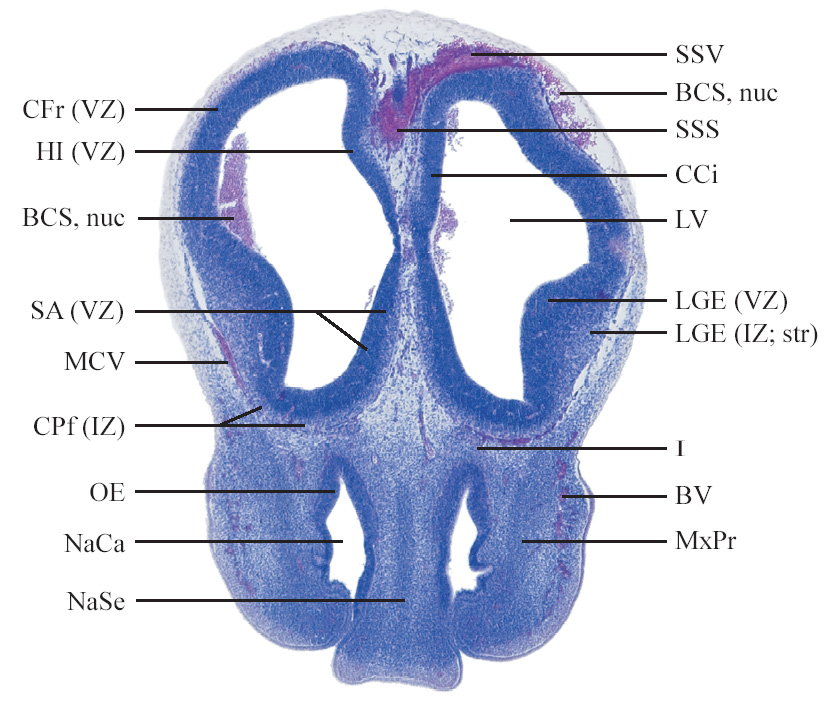

C57BL/6J GD12 Mouse Brain Atlas

Slides from U. Schambra, coronal cuts with slides at every 5th section, with a hematoxylin and eosin (H & E) stain

Currently on section 45.